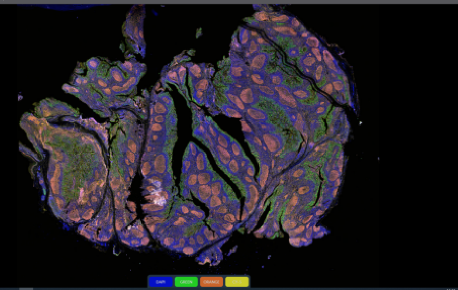

Fluorescence Scanning Features

KFBIO Digital Pathology Slide Scanners (fluorescence) have excellent performance in the accuracy of movement, focus, and image processing, and its accurate whole slide imaging not only meets the requirements of digital slide viewing and operation but is also suitable for AI-assisted image analysis.

Excellent Cross Color Suppression Design

Independent LED light source avoids cross color. High contrast, high brightness, no drift, and no cross color make it more suitable for specific fluorescence channels. Equipped with CHROMA filter narrowband filter, the minimum spectral band resolution reaches 10nm, which can efficiently separates different fluorescence channels to achieve large information density without affecting the quality of data.

Image Processing Algorithm

The fluorescence image stitching algorithm based on high-precision direct position feedback is used to splice images to obtain seamless whole-slide images and improve browsing experience. Pupil function of visual image enhancement algorithm is applied, no need to correct slides. The optical field information is efficiently estimated based on the limited excitation light information. When the light field information does not change with the increase of new sample, the light field information must be the right one for the set of optical path, and the light field can be calibrated based on this information.

Multiplex immunofluorescence scanning

FISH scanning analysis

Scientific research applications:

brain research, liver and stem cell research,

drug research and development

Tumor micro environment analysis/

spatial transcriptome analysis